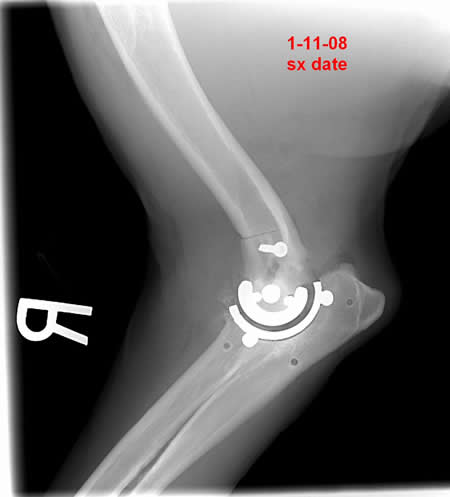

Orthopedic interest started in veterinary school preparing skeletons and bone models for professors. Orthopedic interest led him to many specialized teaching courses including hip replacement (CFX, BFX, and KYON), elbow replacement (Iowa State and Lewis), ACL repair (TPLO and TTA), spine and most fracture management systems. Currently he practices in Sun Valley doing orthopedic referral cases. He practices with his two brothers who are veterinarians and will soon be joined by two daughters who are in veterinary school. Recently he developed the TATE Elbow™ .

It is a minimally invasive resurfacing arthroplasty of the canine elbow.

When was the first clinical case?

In July of 2007 we implanted “Otis” who was an older Labrador with many orthopedic problems. I was apprehensive, with a client owned patient, but the owner was aware of the experimental nature of the case and was frustrated with his dog’s inability to move. With two engineers in the room and a three hour surgery, I was relieved to get the implant in. I was more relieved when he walked out of the clinic three days later bearing weight well. I had researched other systems that had been discontinued after only a few cases. I was recently contacted by the owner requesting the other elbow be replaced.